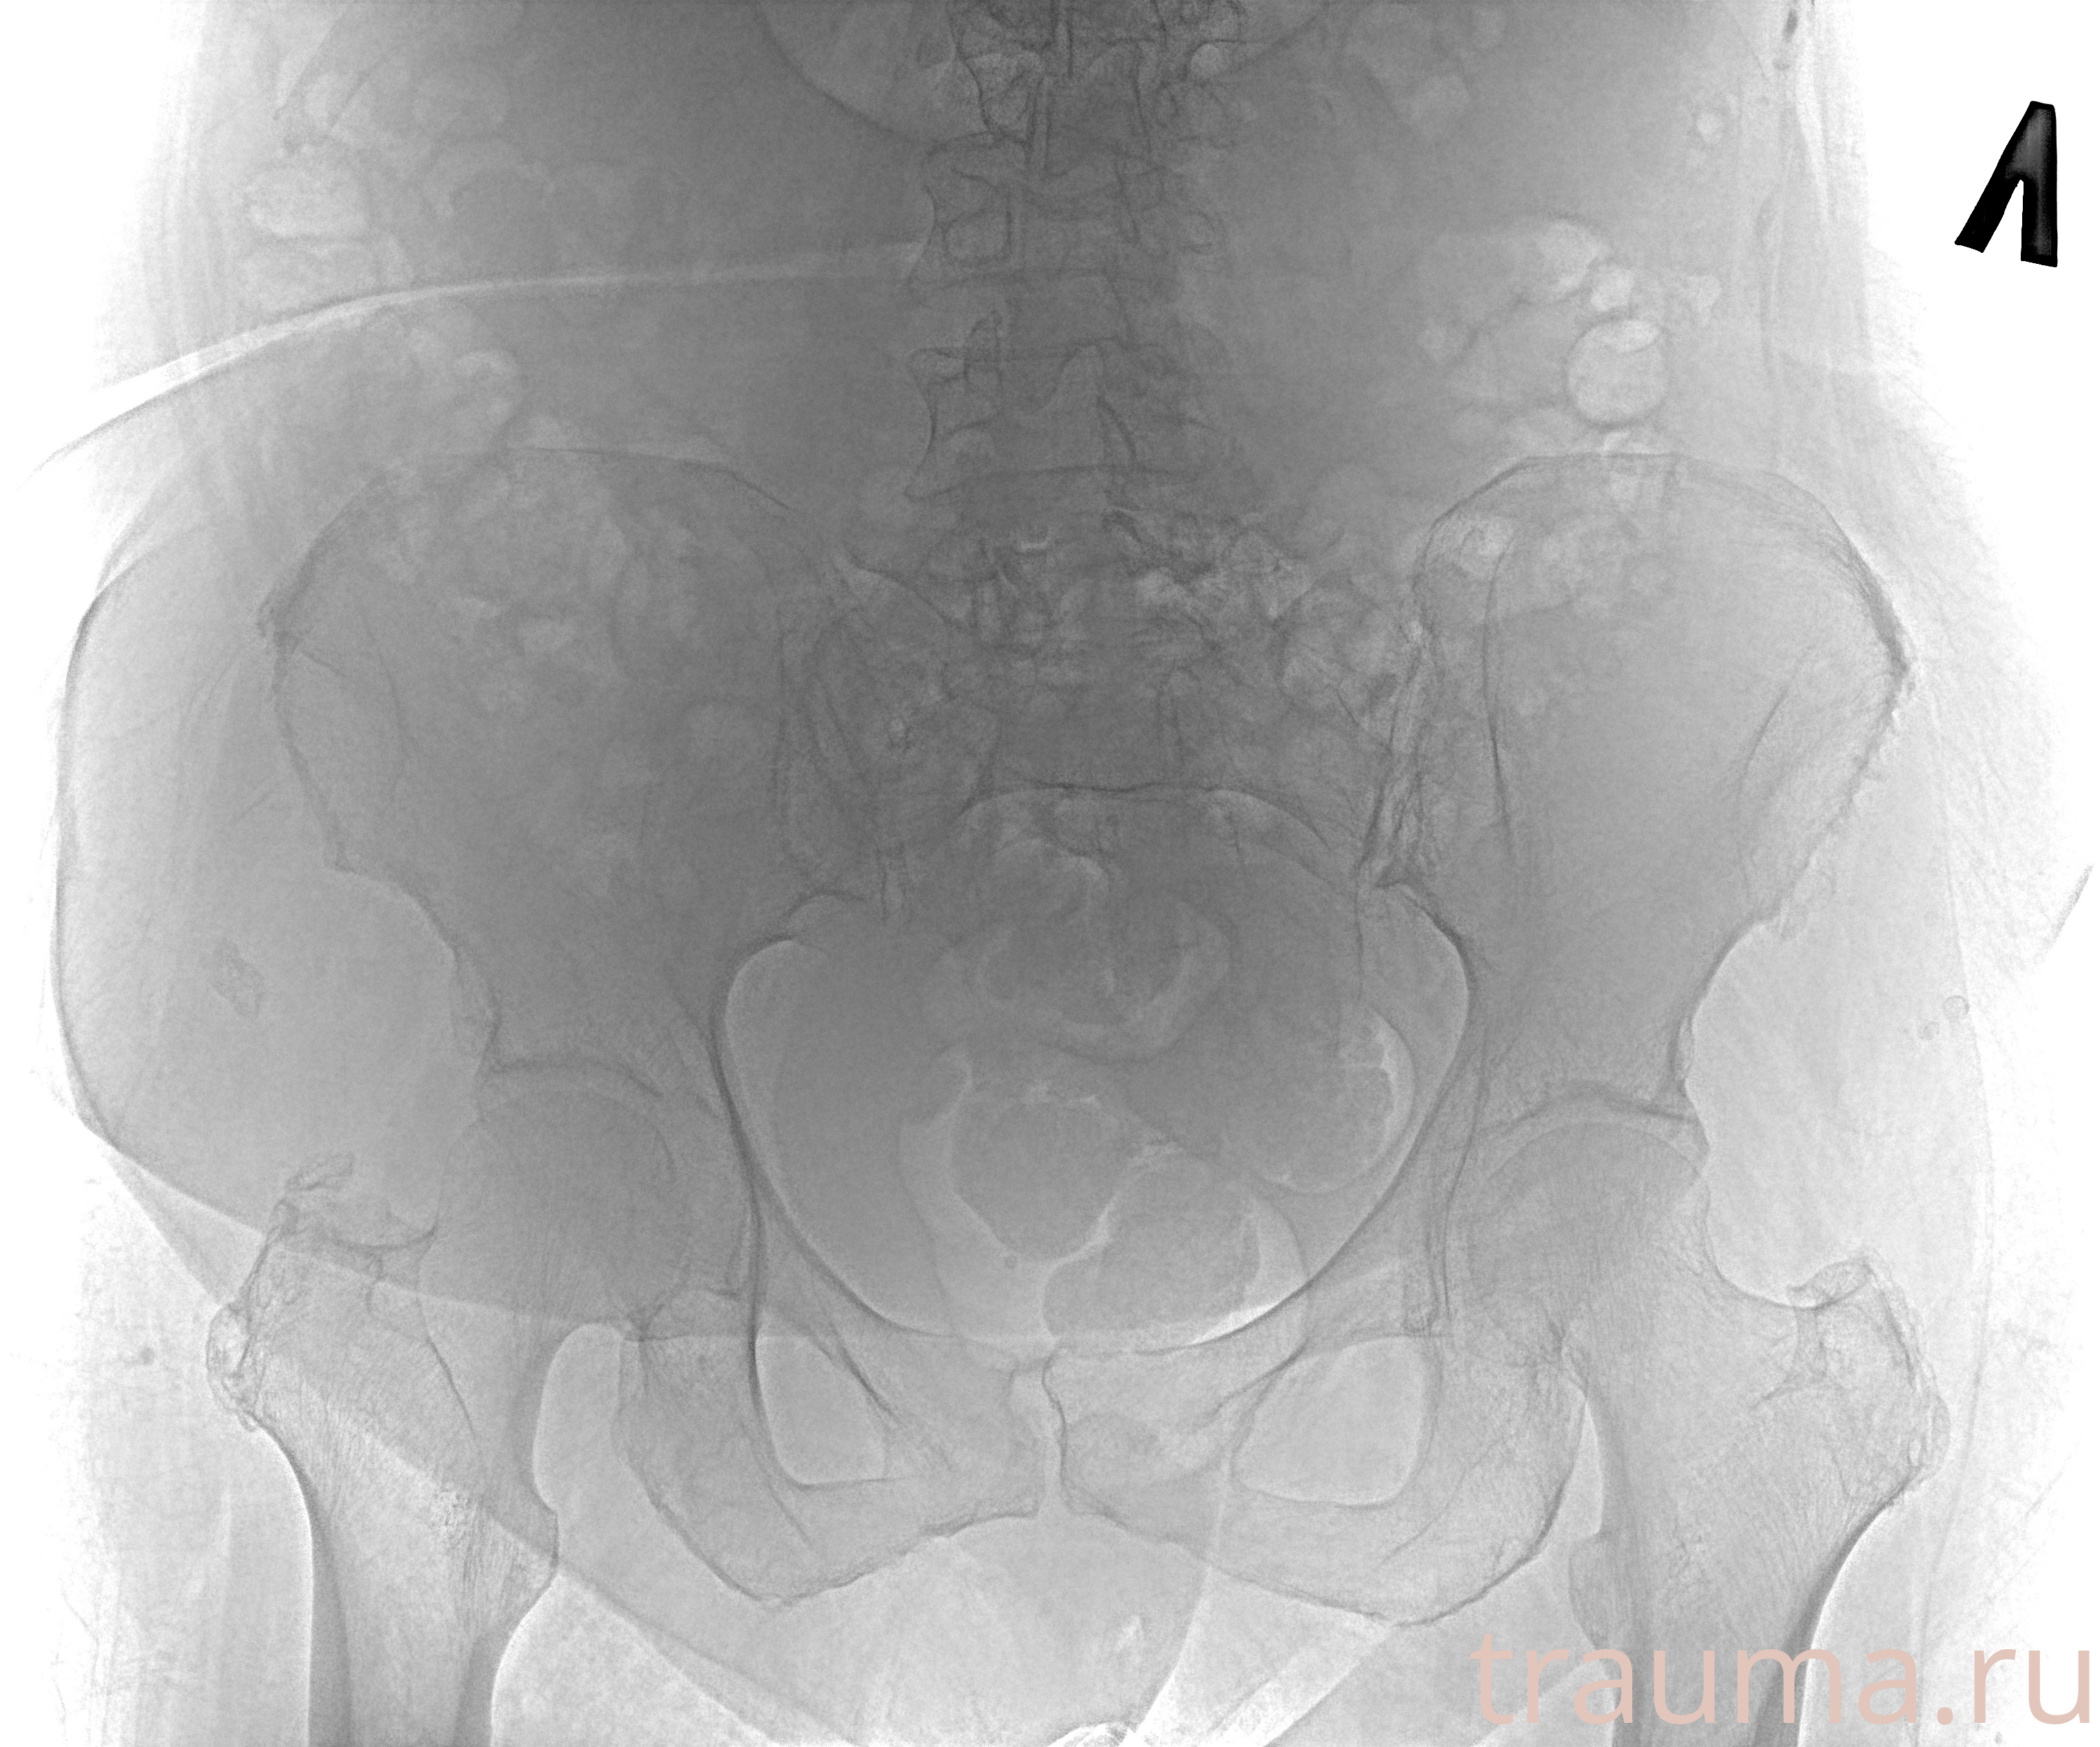

Рентгенограммы

Рентген на дому: по вашему адресу приезжает врач-рентгенолог, травматолог-ортопед с мобильным рентгеновским аппаратом, проводит диагностику травмы или заболевания, делает необходимые рентгенограммы, дает рекомендации по дальнейшему лечению. Получить качественные снимки в домашних условиях возможно благодаря уникальной методике, разработанной МосРентген Центром для института  Склифосовского